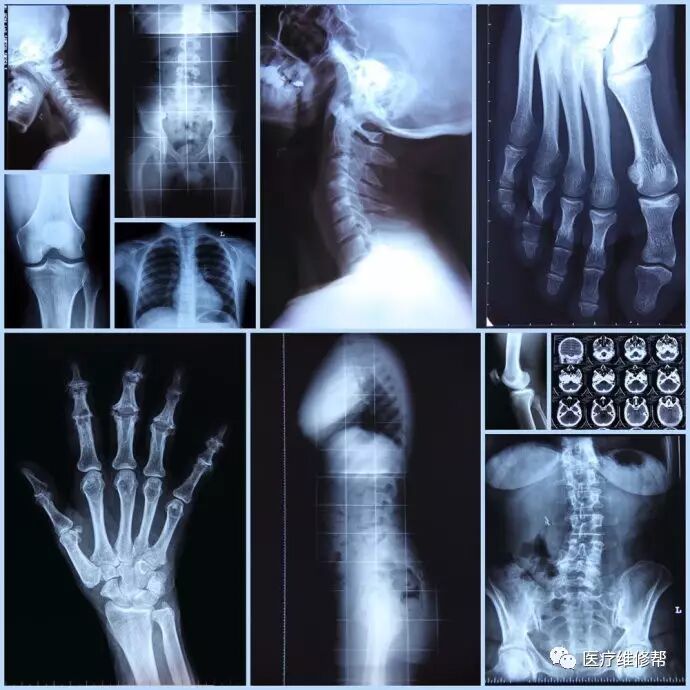

X线机是医学上六大成像设备之一,是诊断疾病的常用工具,也是各医院的经济增长点。

X光区别于CT、B超、MRI的地方是X光可以穿透人体。被遮挡的部位,底片上不会曝光,洗片后这个部位就是白色的。X光受限于深浅组织,其影像相互重叠和隐藏,有时需要多次多角度拍摄X光片,才能看清楚。

X光产品最常见的有血管造影机、移动DR、CR、骨科C型臂、胃肠机、乳腺机、床旁机等等。

数字化图像对骨结构、关结软骨及软组织的显示优于传统的X线成像,还可行矿物盐含量的定量分析。数字化图像易于显示纵隔结构如血管和气管。对结节性病变的检出率高于传统的X线成像,但显示肺间质与肺泡病变则不及传统的X线图像。DR在观察肠管积气、气腹和结石等含钙病变优于传统X线图像。